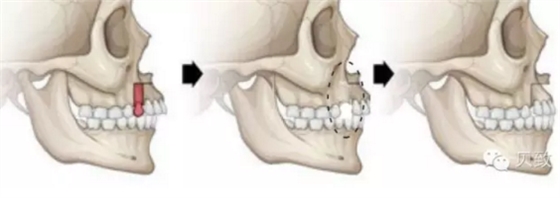

矯正時牙齒之所以能在口腔中移動,主要是因為包裹牙根的牙槽骨具有終生改建的能力。牙槽骨的重建作用,有點類似于“拆東墻補西墻”。

當(dāng)牙齒向前移動,持續(xù)的壓力作用到牙槽骨上時,受力部分的牙槽骨會逐漸被吸收,給牙齒的移動開辟了空間。而包繞在牙齒后側(cè)的韌帶會受到牽拉,提示它需要修復(fù)因牙齒移動所產(chǎn)生的縫隙啦,機體立即會長出新的牙槽骨來填補多出來的空隙!這么一吸一補,牙齒就能在牙槽骨中穩(wěn)穩(wěn)地移動啦~

在改建周期完成以后,這顆牙齒依然被牙槽骨緊密包圍,不留空隙,但位置已經(jīng)產(chǎn)生變化了,完美解決牙列缺損、擁擠問題,何來牙齒傾斜松動一說?